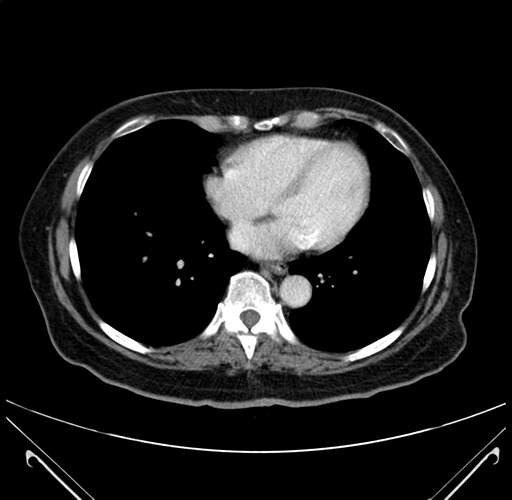

Pre-Chemo: Axial Venous

Axial Venous